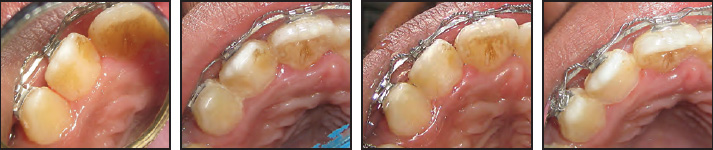

After extraction of the four first premolars, orthodontic treatment was initiated with standard edgewise brackets. Because of the anterior cross-bite, there was no occlusal interference from the talon cusp at first. After initial leveling and alignment, however, the cusp came into contact with the opposing teeth (Fig. 3), and the patient was referred to the Department of Conservative Dentistry and Endodontics for appropriate treatment.

The lateral incisor was causing no pain or discomfort, and vitality tests using an ice stick were positive. The patient was prescribed desensitizing toothpaste at the start of the talon-cusp treatment. At the first appointment, the palatal projection of the talon was ground enough to eliminate the premature contact. Thereafter, the talon cusp was reduced gradually, using a watercooled, flame-shaped diamond bur in a high-speed handpiece, at six-to-eight-week intervals (Fig. 4).

Fig. 3 Dental casts show occlusal interference from talon cusp after initial leveling and alignment.

Fig. 4 Talon cusp reduced by grinding over four consecutive appointments at six-to-eight-week intervals.